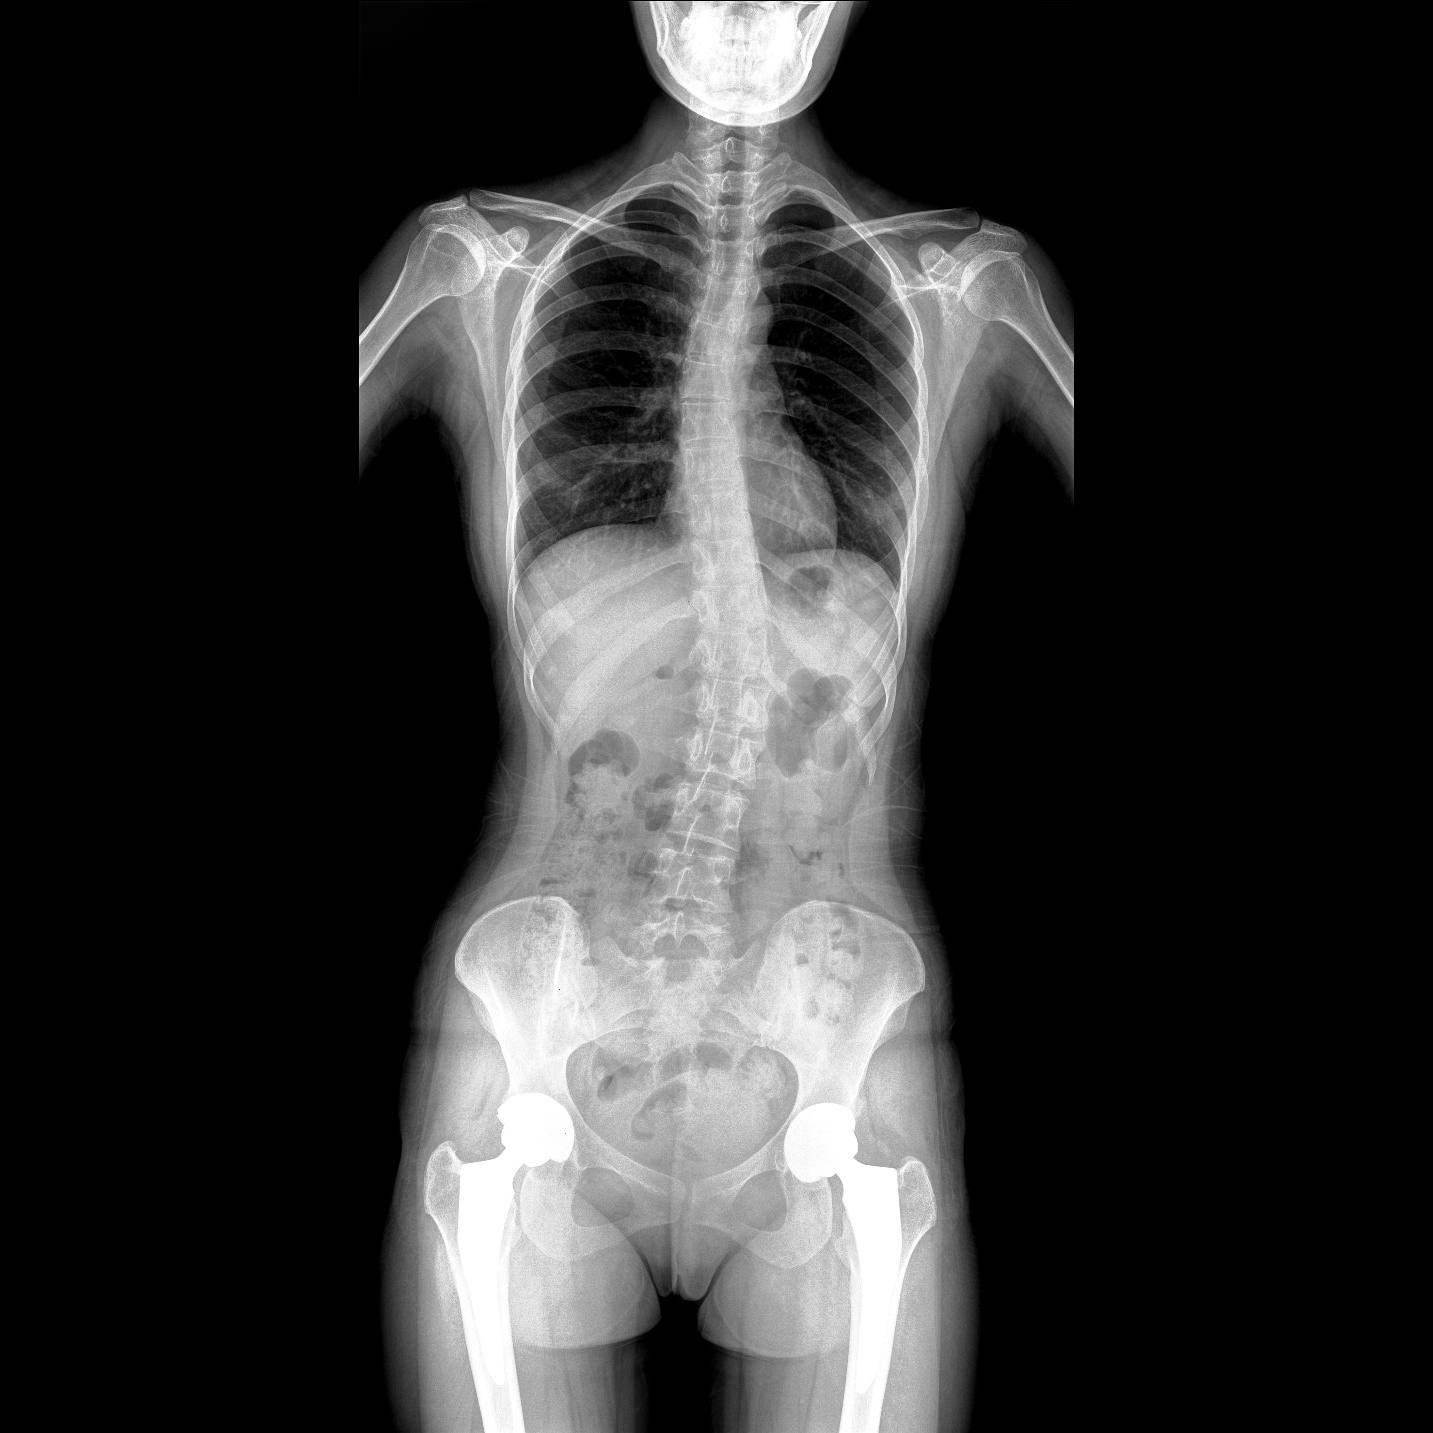

17"*34"有效視野,一次成像不拼接。相較于多張攝影再軟件拼接的DR設備,PLX8600解決了拼接圖像存在密度不均勻,拼接處圖像配準和放大效應等問題,給臨床帶來了大視野影像解決方案,可一次性覆蓋全脊柱或雙下肢影像。

除常規靜態攝影外,PLX8600大平板具備動態透視和點片功能,透視采集功能可支持大視野、多角度的可視化觀察。通過可視化的動態影像,配合點片功能,能夠很好的觀察復雜部位病灶,有效的抓取關鍵幀,降低患者多次攝片的概率。如:全脊柱狀態評估、長骨關節活動度、下肢靜脈造影瓣膜功能評估、消化道功能評估、脊髓造影等更多大視野臨床應用。